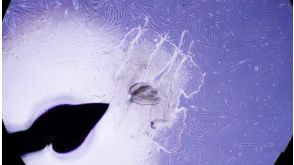

科学海报Generation and Characterization of a Homogenous Population of Early Mesoderm Cells Using STEMdiff Mesoderm Induction MediumConference:

ISSCR 2015; TMM 2015